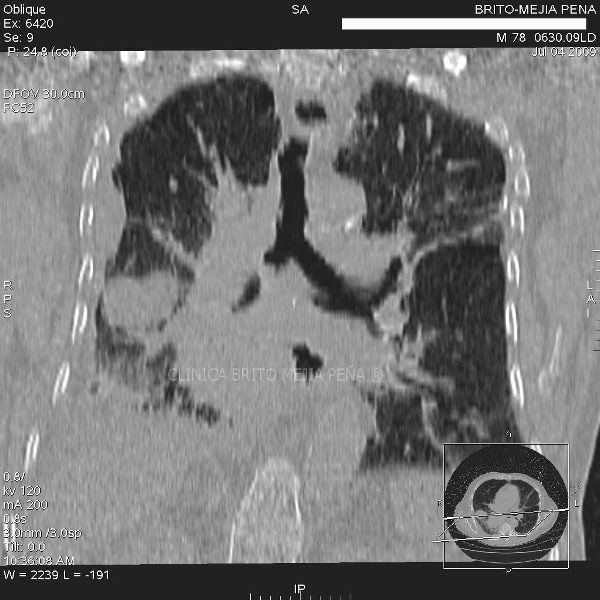

Cáncer Pulmonar Coronal